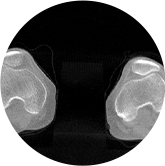

膝关节